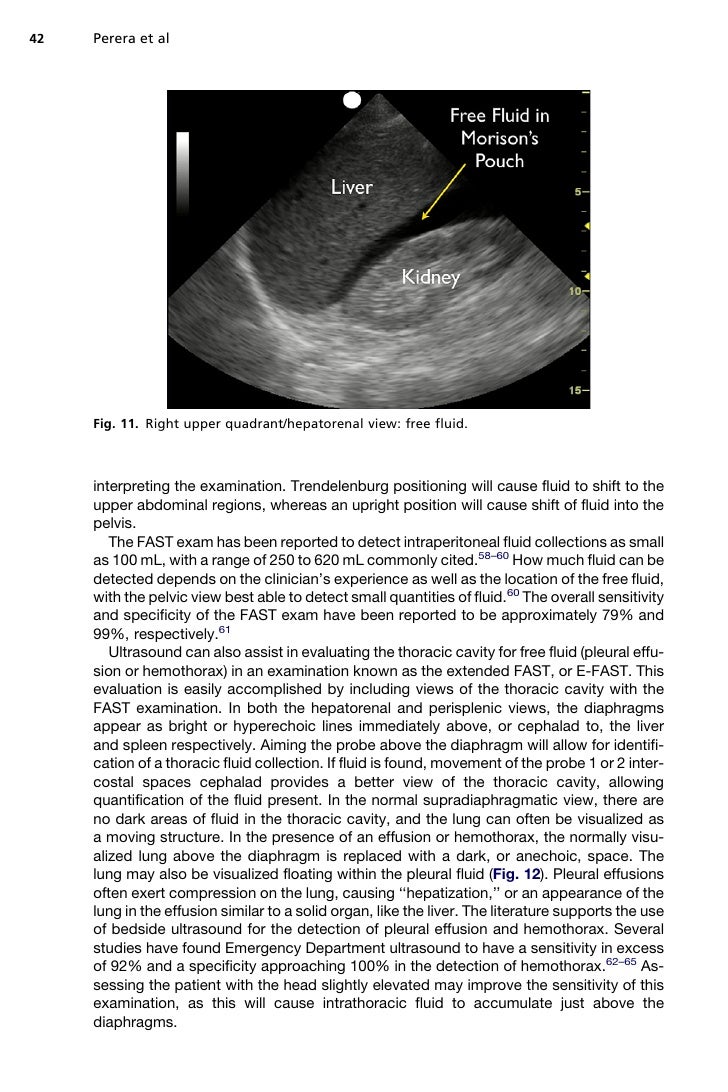

Work on this for 2 days before an exam. What are the components of the rush exam? The majority of ruptured aaa are retroperitoneal therefore when performing the fast exam, no intraperitoneal free. Rush è un pronto strumento diagnostico che permette di effettuare una corretta diagnosi, con la visualizzazione diretta e/o indiretta delle cause. September 12, 2016 samuel schiff.